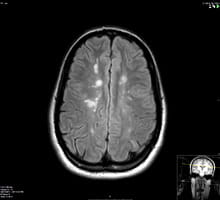

An MRI image showing a long area of inflammation in the spinal cord of a patient with NMO

An MRI image showing a long area of inflammation in the spinal cord of a patient with NMO.

Neuromyelitis Optica (NMO) or Devic’s disease is a severe autoimmune inflammatory condition that preferably involves the optic nerves and the spinal cord causing extensive inflammation and tissue damage. It is caused by specific antibodies against water channels in the central nervous system and often leads to significant disability if not treated aggressively and in a timely manner. NMO is more common in African American and Asian populations and is not uncommonly misdiagnosed as MS which can lead to improper and potentially harmful treatment. Learn more about Neuromyelitis Optica.